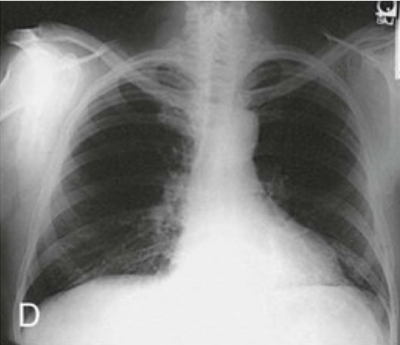

Question 9

Question

Identify the body habitus

Answer

• Hyposthenic

• Sthenic

• Asthenic

• Hypersthenic